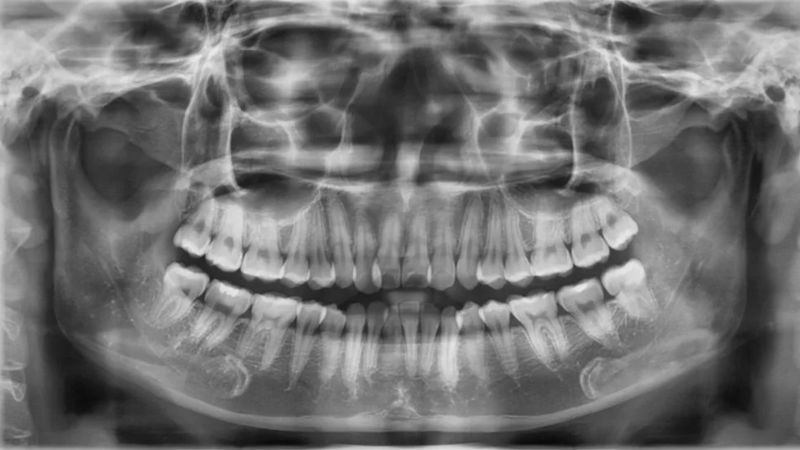

Với sự tiến bộ của công nghệ hiện nay, quy trình nhổ răng hàm bị sâu đã trở nên nhẹ nhàng hơn nhiều so với suy nghĩ của nhiều người. Trước khi thực hiện, bác sĩ sẽ tiến hành kiểm tra tổng quát và có thể yêu cầu chụp X-quang hoặc làm các xét nghiệm khác nếu cần thiết.

Ngược lại, trong những trường hợp sâu răng gây viêm nặng, nhổ răng sâu có thể là giải pháp tối ưu. Sự phát triển của sâu răng có thể dẫn đến việc vi khuẩn tấn công vào chân răng và xương hàm. Bác sĩ có thể quyết định nhổ răng nếu tình trạng này nghiêm trọng, đặc biệt là khi chân răng bị tổn thương, có hiện tượng tụt lợi hoặc viêm nha chu.